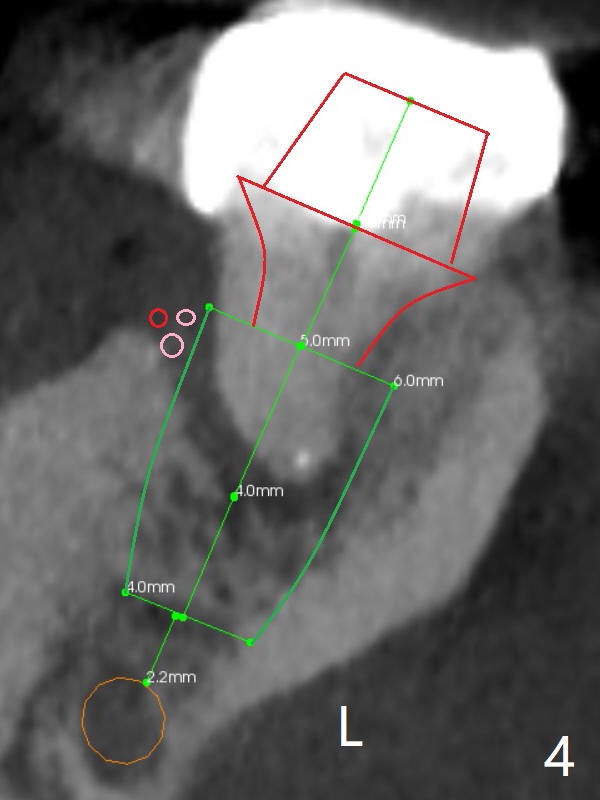

A 53-year-old man will return for #18 extraction and implant because of endo failure after the same treatment at #14 (Fig.1). It appears that the mesiolingual canal is missing for RCT (Fig.2 (coronal section at the mesial root)). Bony defect is buccodistal; try to place an implant as mesiolingual as possible (Fig.3 (axial section)). To reduce lingual (L) plate perforation and neuropathy (orange), the implant is expected to be 5-6x9 mm (Fig.4,5). Use 4 mm stopper from DIO Sinus Kit for osteotomy (Fig.1,4,5). If his vein is prominent, prepare PRF 1-2 tubes.